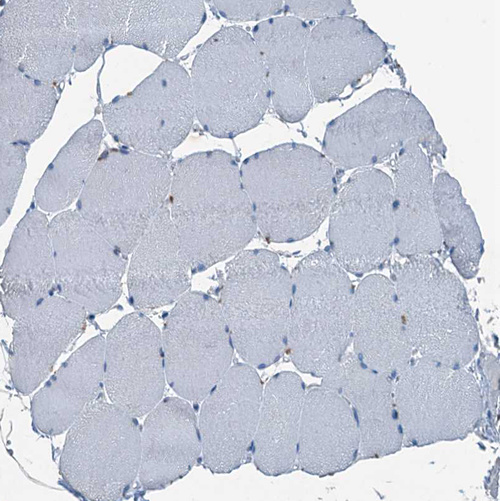

Immunohistochemistry analysis in human stomach and skeletal muscle tissues using HPA039908 antibody. Corresponding GIF RNA-seq data are presented for the same tissues.